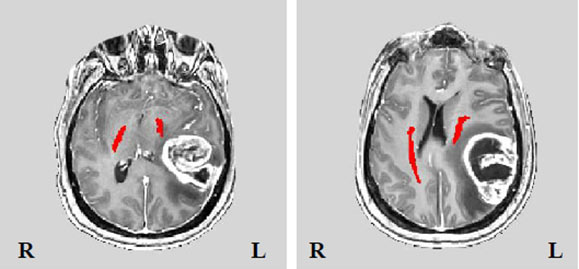

ההכנה לניתוח הוא שלב חשוב בתהליך. הוא כולל סדרת בדיקות שמטרתן להבין את מיקום הגידול ואת הקשר שלו לאזורים תפקודיים. בדיקות אלו כוללות הדמיה מוחית CT מוח, MRI מוח כולל DTI להדגמת מסילות חומר לבן בקרבת הגידול (תמונה מס' 2). בנוסף, אנו מבצעים הערכות נוירופסיכולוגיות להערכת תפקוד קוגניטיבי, וכן בדיקות דם והערכה רפואית כללית. תהליך זה מאפשר תכנון ניתוח מדויק ומותאם אישית לכל מטופל.

תמונה מס' 2: מסילות מוטוריות (באדום) בקרבת מוחי גידול משמאל